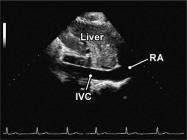

| 2.25. Mặt cắt dưới sườn cắt dọc tĩnh mạch chủ dưới (video 66) |

||||||||

|

|

Cửa sổ siêu âm dưới sườn

Ghi hình tĩnh mạch chủ dưới Cắt theo trục dọc của cơ thể người bệnh |

Tĩnh mạch chủ dước (IVC) cắt dọc | |||||